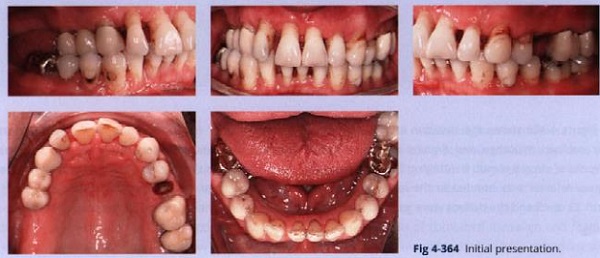

Người đàn ông lớn tuổi này có tình trạng xương bị tiêu với răng trồi và những khoảng ở cả hai cung (hình 4-364).

Bệnh nhân có những dấu hiệu của CMD với lệch vị trí đĩa về phía trước mà không trở lại vị trí và đau đầu.

Chẩn đoán:

• CMD với sự dịch chuyển đĩa về phía trước mà không trở lại vị trí trước đó

• Đau đầu

• Viêm quanh răng

• Cắn sâu và mất sự hỗ trợ phía sau ở tương quan tâm

• Răng chen chúc